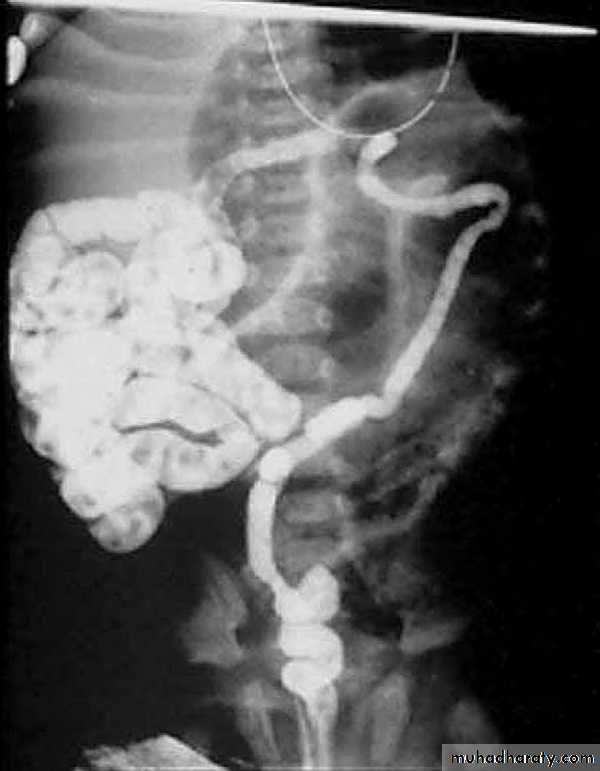

• 2.contrast (barium) enema: small unused microcolon

Treatment

1.nonoperative management:Rehydration, Broad spectrum antibiotics coverage .

Gastrographin enema under fluoroscopy .

3.Operative management:

Enterostomy & removal of meconium.Resection with end to end anastomosis .

Bishob Koop or santulli anastomosis.